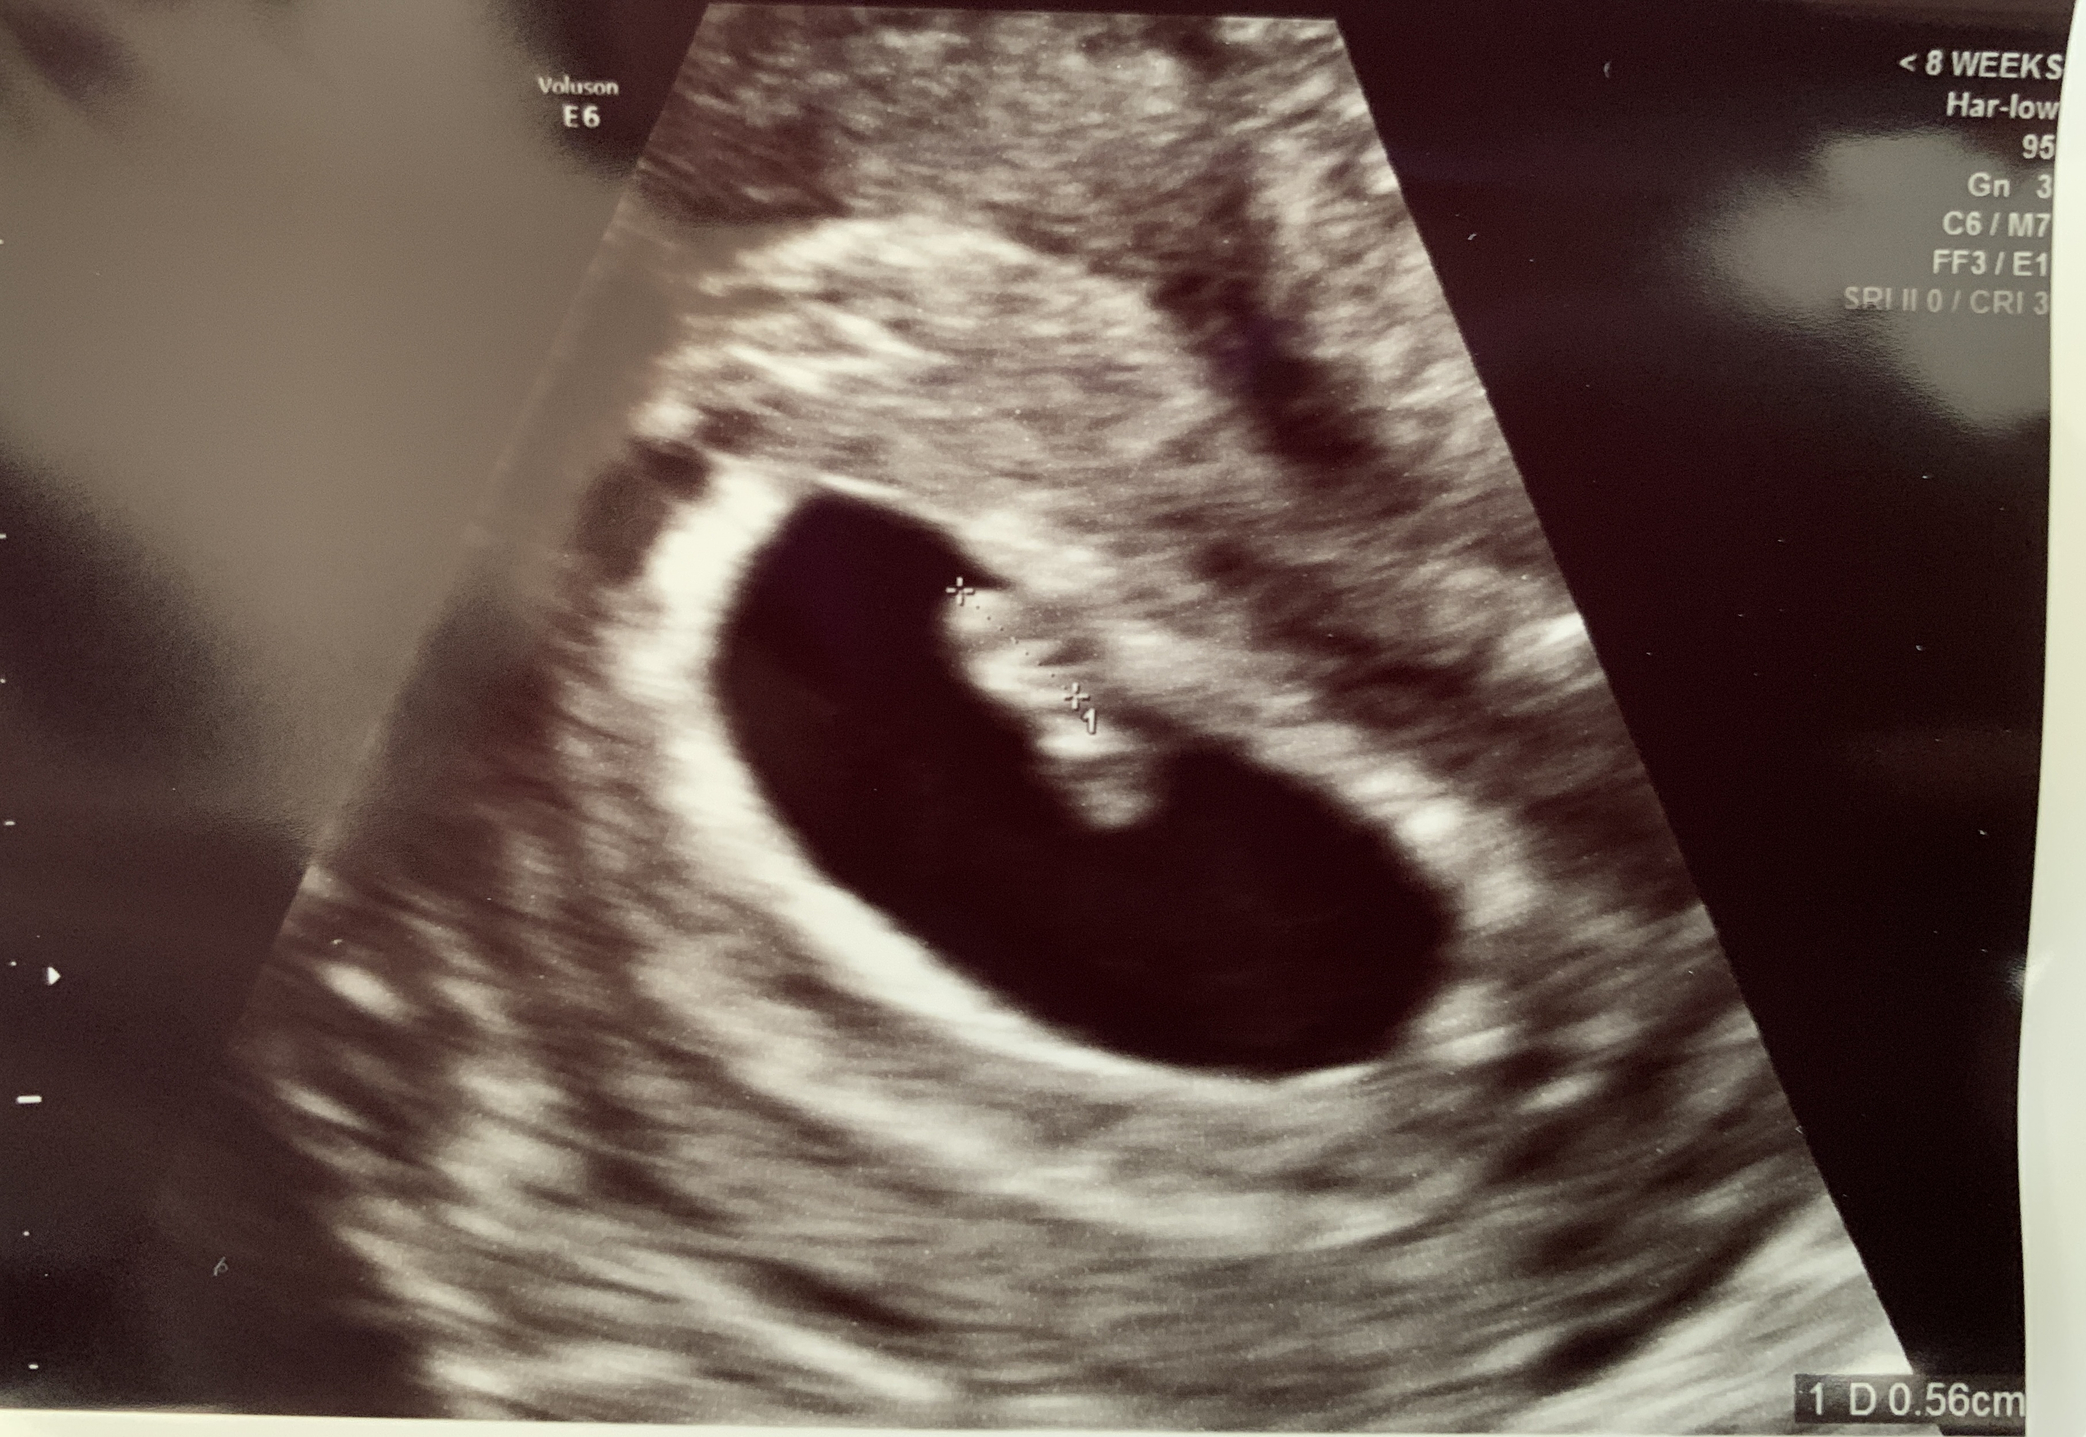

Had first US on 12-28. I thought I was 8wk3d but they dropped it all the way back to 6wk5d. It was quite disheartening to go back that much. But happy to see that everything and baby looks healthy. Was able to see the little flutter of a heart beat.💜 But didn’t get to hear it.